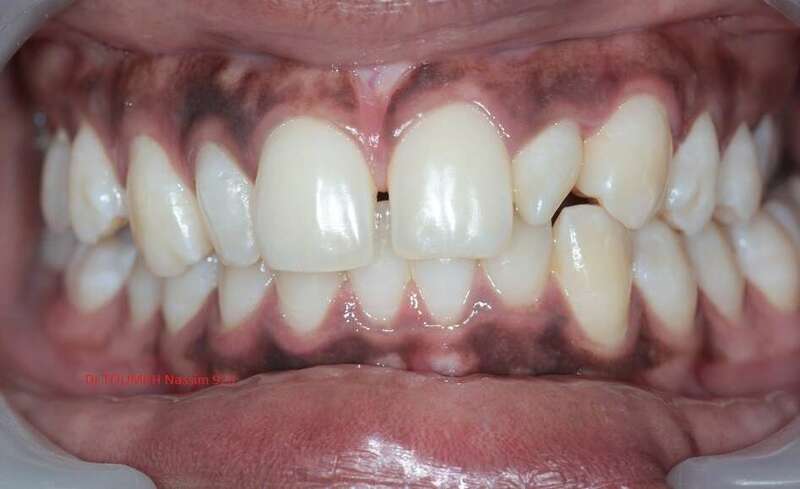

Latérales naines et orthodontie

la forme des dents influence grandement l’esthétique du sourire

La malformation des incisives latérales en est l'illustration

Le traitement consiste à redresser les dents à l'aide d'un appareil orthodontique (Multiattaches) et à redonner une forme normale aux dents malformées.

Dans ce cas présenté des couronnes provisoires en résines ont été posées.